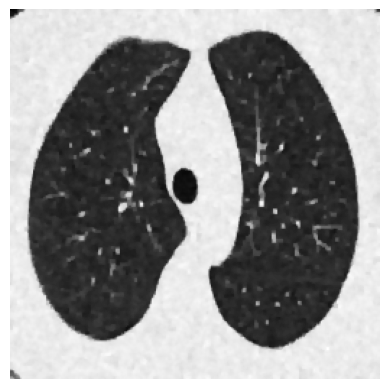

In Section 6, we validate our learned algorithms on two inverse problems: image deblurring and Computed Tomography (CT). Inverse problems represent a crucial class of optimization problems that appear in important fields such as medical imaging and machine learning. Many such problems have an associated forward operator which is highly ill-conditioned, making them an ideal test for optimization algorithms.